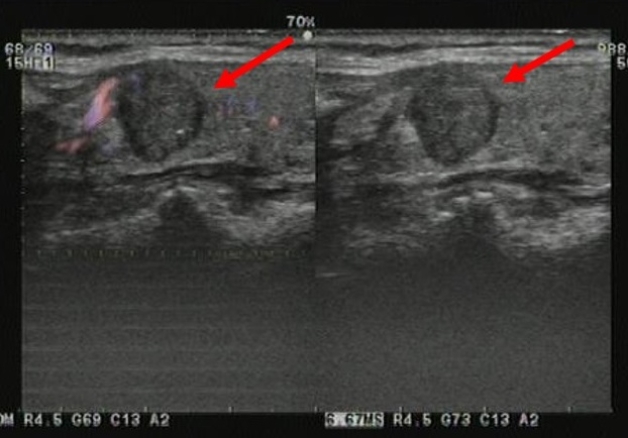

Hình ảnh nhân đặc được xác định thông qua siêu âm